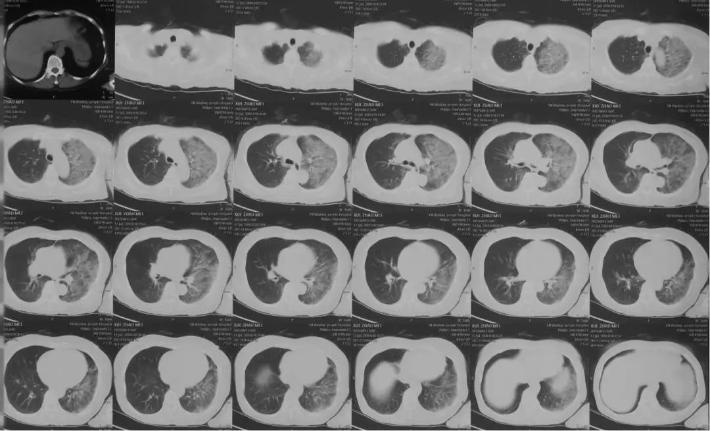

侧脑室穿刺引流术后复查头颅CT

复查胸部CT